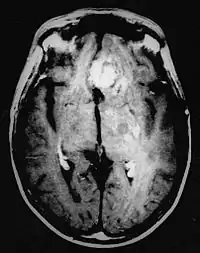

En las imágenes de TC y RM se muestra como una lesión heterogénea, de contorno irregular, que capta contraste en anillo y con un área central necrótica.

Diagnóstico por imagen y glioblastoma

La TC muestra una lesión de morfología irregular, predominantemente hipodensa y fuertemente dishomogénea, debido a la presencia de grandes áreas necróticas de más clara hipodensidad y de áreas sólidas hiperdensas. Estas últimas son la expresión de un rápido crecimiento y por lo tanto de una elevada malignidad. Son frecuentes las zonas hemorrágicas, que van desde pequeños focos a grandes áreas hemáticas que pueden cubrir toda la lesión. Es característica la morfología en "mariposa" si el tumor se asienta en ambos hemisferios a través del cuerpo calloso.

Tras la aplicación de contraste aparecen gruesos anillos alrededor de las áreas necróticas. En la RM, la parte sólida aparece hipointensa en T1 e hiperintensa en T2 con zonas de señal más elevada en las partes de mayor celularidad. Las áreas necróticas, hiperintensas en T2, pueden presentarse hipo-, iso- o hiperintensas en T1 en función del contenido proteico o de productos de la degradación de la hemoglobina. El realce tras el contraste suele ser intenso e irregular en la periferia del tumor e identifica sobre todo la componente celular "proliferativa" de la neoplasia. Son comunes las áreas puntiformes y serpiginosas de ausencia de señal de flujo, asociadas a la presencia de una neovascularización rica. Estos vasos de neoformación patológica carecen de barrera hematoencefálica, lo que explica tanto la abundante impregnación como el edema vasogénico perilesional (véase la sección anterior), debido al paso de líquido al medio extracelular.[71][72]